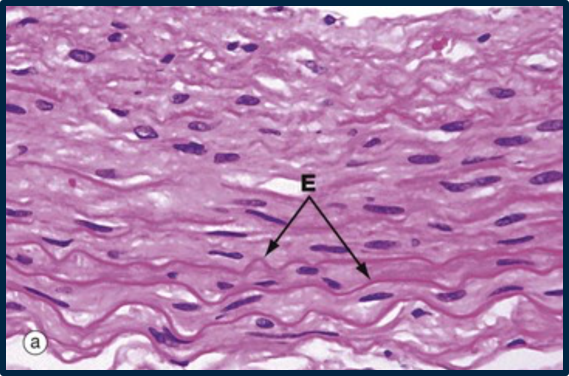

thick sheets of elastic fibres with wave like conformation. this is a relaxed artery wall with the cells between the elastin as smooth muscle cells

How well did you know this?

E is elastin

L is collagen